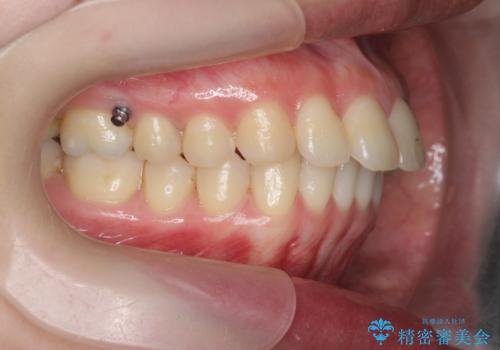

カリエール・マイクロインプラントを併用した歯の突出を改善する大きな遠心移動

- 口が閉じづらく、突出し歯が出っ歯に見えてしまうことの改善を求めて来院されました。

通常このような場合、抜歯してのワイヤー矯正治療も選択肢に入りますが、患者様の強い希望により抜歯を行わずマウスピースによる治療を選択しました。

カリエール・マイクロインプラントを用い、時間はかかりましたが大きく歯の後方移動が達成され、前歯の見た目が大きく改善されました。